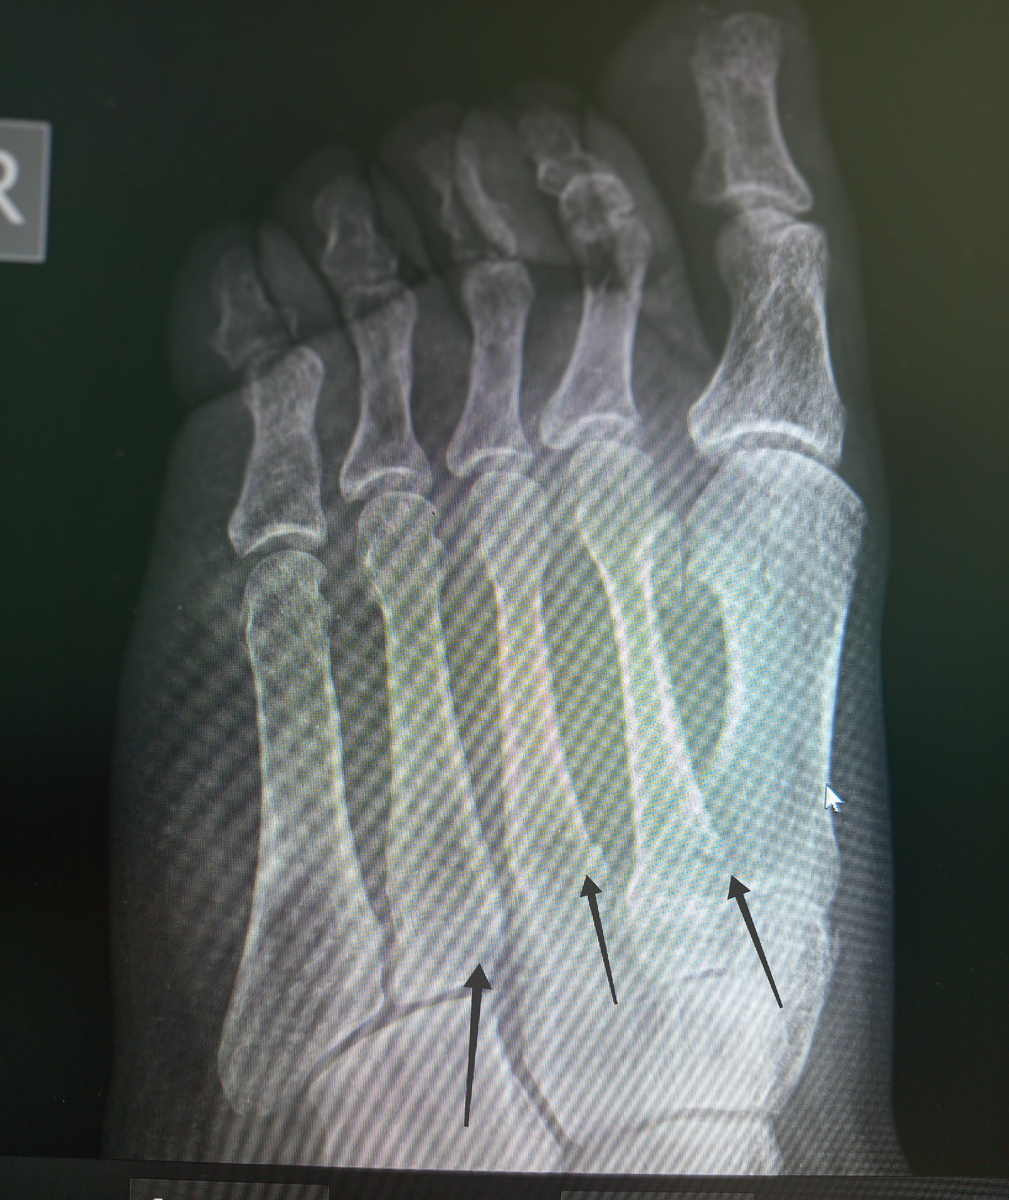

Завезли каталку, мужчина , 44 года. Был сбит на пешеходном переходе, в анамнезе инсульт , телом управляет плохо, сопровождает жена.

Назначили снимки черепа , лёгких , таза и стопы.

Из всего только в стопе кости и сломаны.

Хромая , заходит мужчина, 36 лет , на снимок стопы. Первый и второй палец фиолетового цвета.

–Что случилось?

–Нет, болты не смог открутить, психанул и пнул ее в сердцах.

Понял , что это было лишнее, когда пальцы приобрели цвет. Ну , так , нечего стопы распускать!

Кости целые, просто ушиб, а вот выходные испорчены, ушиб -то тоже болит!

Еще мужчина на снимок стопы.

–Плитка упала , прямо краем воткнулась.